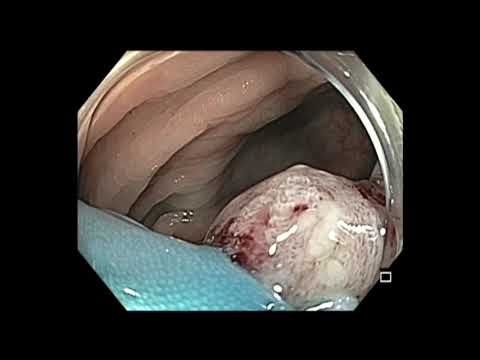

Papillektomia u pacjenta z rodzinną polipowatością...

W filmie pokazano zabieg endoskopowej papillektomii (resekcji brodawki Vatera) u pacjenta z rodzinną polipowatością gruczolakowatą (FAP).